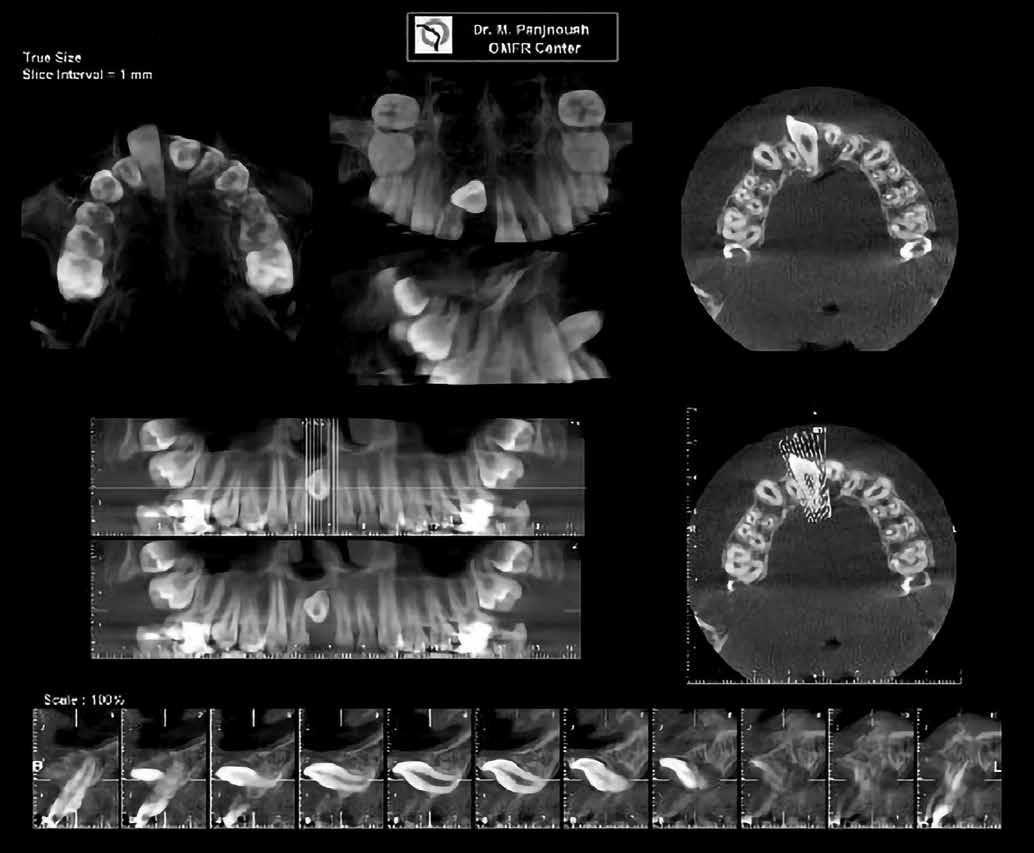

A 10 éves férfi páciens a felső frontfogai késői/nem megvalósuló előtörése miatt kereste fel a rendelőnket. A klinikai és a radiológiai vizsgálat során a jobb felső nagymetszőfog impakcióját észleltük (1. ábra). A fog horizontális tengelyállással és dilacerált gyökérrel rendelkezett. A felső dentális középvonal a fogak vándorlása miatt jelentős mértékben elcsúszott. A bal felső kismetszőfog is rendkívül kedvezőtlen pozícióba került.

1. b ábra: A panoráma röntgenfelvételen megfigyelhető a teljes impakcióban lévő jobb felső nagymetszőfog. 1. c ábra: A CBCT felvétel is igazolja a jobb felső nagymetszőfog impakcióját.

4. a ábra: A CBCT felvétel igazolja, hogy a jobb felső nagymetszőfog megfelelő pozícióba került. Az ínyszél lefutása kedvező, a fog gyökere körül elfogadható mennyiségű csontállomány ábrázolódik, valamint a gyökérfelszívódás mértéke sem túl kifejezett.

6 hónapon keresztül tartott. Ennek megfelelően a fog körül található szövetek a felszabadítás, valamint a havi kontrollok során 975 nm-es (több mint 25 J/cm2 energiasűrűség) és 660 nm-es hullámhosszúságú (12–18 J/cm2 energiasűrűség) lézersugarakkal is megvilágításra kerültek. Az impaktálódott fogat megközelítőleg 7 hónap alatt tudtuk megfelelő pozícióba mozgatni (3. ábra). Az orthodoncia kezelés aktív szakasza 18 hónapon keresztül tartott. A fogívek végső nivellálását és a fogak végleges pozícióba rendezését 0.018 × 0.025-ös acélívekkel végeztük.

A kezelés befejezésekor a páciens mosolya drámai mértékben javult, továbbá a frontfogak elhelyezkedése és az ínyszél lefutása is szemmel látható módon kedvezőbbé vált (4. ábra). A kezelés végén készült CBCT felvétel nem mutatta

csontfelszívódás jelenlétét, és csupán minimális mértékű gyökérfelszívódás bekövetkezését igazolta.